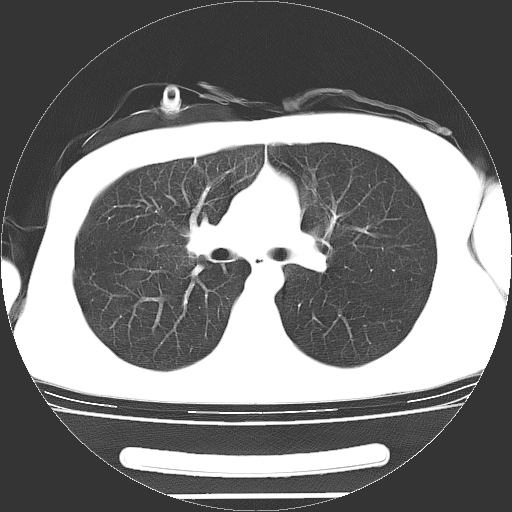

男,20岁,右侧气胸行闭式引流术后五天ct检查看肺内是否有肺大泡,纵隔窗未见异常,未上传。

未见肺大泡影

右肺未见确切肺大泡。

1)右侧胸腔闭式引流术后导管留置。2)右肺未见肺大泡。

未见肺大泡,还有微量气体。